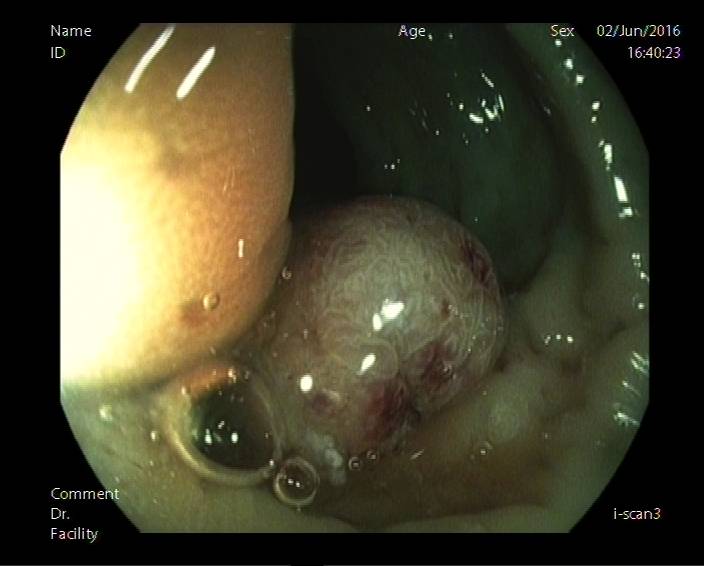

图6a:距肛门3cm可见一直径约4cm隆起,占肠腔1/2,表面粗糙,溃烂。使用蒸馏水对病灶表面冲洗去除黏液,可见病灶表面无构造(无pit)区域或构造紊乱,可初步判定为V型pit。

图6b:观察病灶顶端,仍见无构造区域。依旧考虑V型pit。且病灶位于直肠,病灶表面可见白斑,病灶表面凹凸不平,均提示sm癌浸润可能性大(参考图5),建议外科手术。

后患者就诊于肛肠外科行手术治疗,病理示:1.(直肠)中分化腺癌,部分为粘液腺癌(肿块一个5×4×1.5cm,菜花状),侵及全层,(远、近断端)未见癌,(肠旁)淋巴结见癌转移(12/12)。